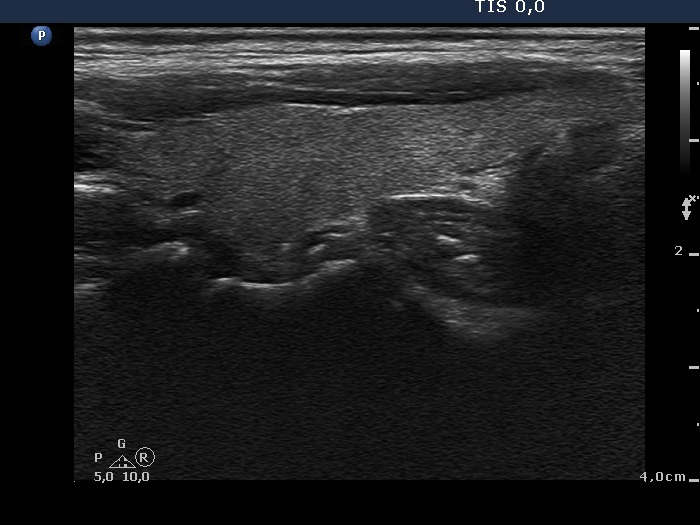

Follow-up examination 3 months later (2nd row of images):

Clinical presentation: The complaints of the patient ceased.

Palpation: The thyroid was not tender, both lobes were firm.

Functional state: hypothyroidism with TSH 2.98 mIU/L and FT4 7.56 pM/L. CRP 1.9 mg/L.

Ultrasonography: The proportion of hypoechogenic areas has decreased. The vascularization became normal.